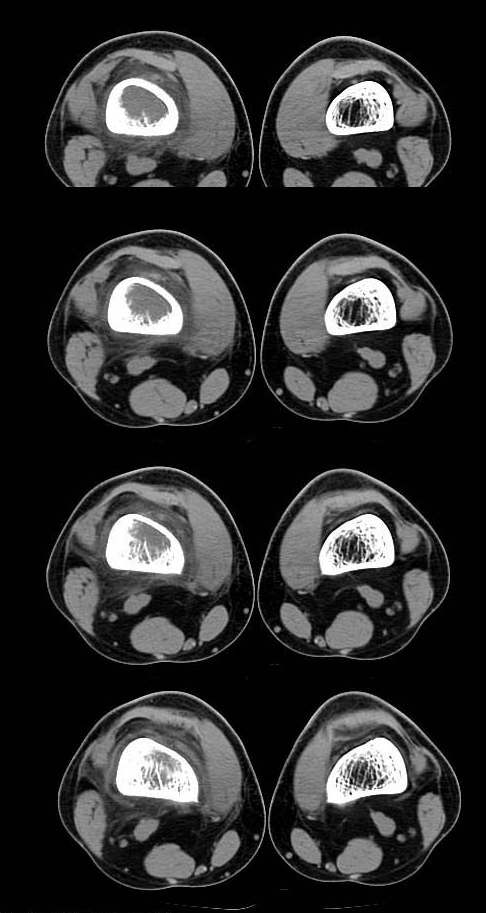

20岁,男,右股骨下端疼痛一个月,无发热,白细胞正常,皮肤不红,肿胀,触痛。

右股骨下端很长范围内的髓腔扩大,骨小梁破坏消失,皮质亦呈融骨性破坏,周围脂肪层次紊乱,肌肉受累及密度减低。考虑为:恶性骨肿瘤。请专家们分析骨肉瘤及尤文氏肉瘤的ct征象。

6.ct及mri:能较好地判断肿瘤的范围及侵犯软组织的情况。mri可见瘤体处广泛性骨质破坏,呈软组织肿块影;在t1加权像上呈均匀的长t1信号;在t2加权像上呈很长t2高信号。在ct上显示为源于骨组织的软组织肿块,骨质广泛破坏。

长骨ct见的较少,该病例股骨下端表现为边缘模糊的溶骨性破坏,伴有费用性脱钙,髓腔密度增高,呈毛玻璃样改变,病变周围软组织肿胀,脂肪间隙模糊,无骨膜反应,应密切结合临床,考虑骨纤维肉瘤或慢性骨脓肿。期待结果。

此病例基本可定是恶性骨肿瘤:髓腔内长范围肿块、皮质不规则破坏、软块及软组织浸润、瘤骨及不规则骨膜反应等。可以肯定地除外炎性病变和骨纤。

结合临床还是将尤文氏肉瘤放在前面,骨肉瘤不排除。纤维肉瘤及恶纤组多见老年人,不放在首要诊断范围内。